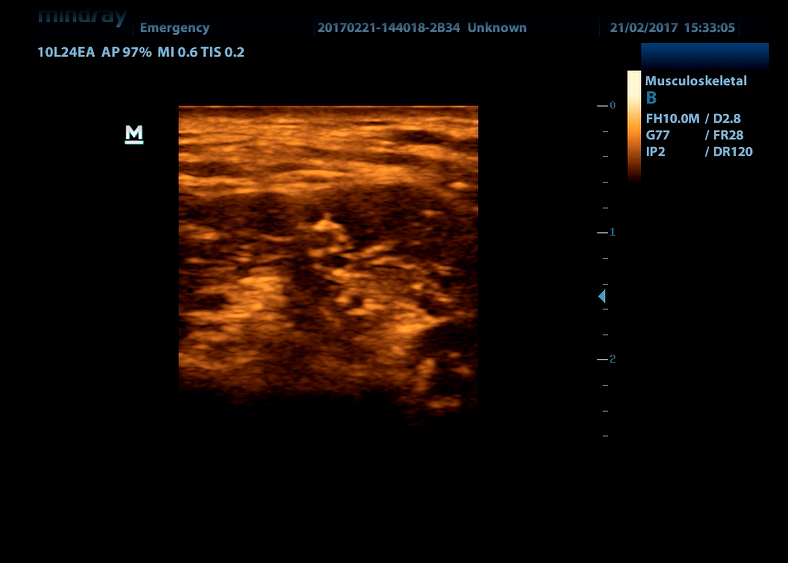

Линейный датчик высокочастотный 10L24EA (8.0/10.0/12.0/14.0/Н10.0/Н12.0 МГц, 24 мм)